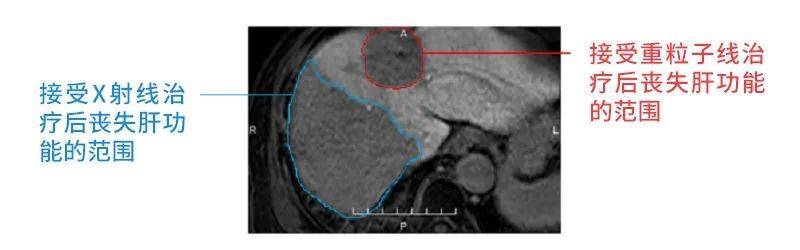

这张图片是一位患有两次肝细胞癌患者的肝脏核磁共振图,该患者接受了两种放射治疗:重粒子线治疗和X线放射治疗。红线代表接受重粒子线治疗后丧失肝功能的范围,蓝线代表接受X线放射治疗后丧失肝功能的范围。

为了让更多的X射线照射癌组织,需要从多个方向分散照射。而X射线能够穿透人体,因此,X射线经过的大面积区域都会被影响,受到损伤。另外,从这张图片中可以看出,重粒子治疗的照射范围比X射线治疗的照射范围窄小。

具有布拉格尖峰的粒子线治疗,在经过布拉格尖峰后对细胞的影响大大降低,所以粒子线治疗对正常组织的损伤较小。由此可见,粒子线治疗的优点是,在布拉格尖峰以外的部分对正常组织的影响小于X线放射治疗。